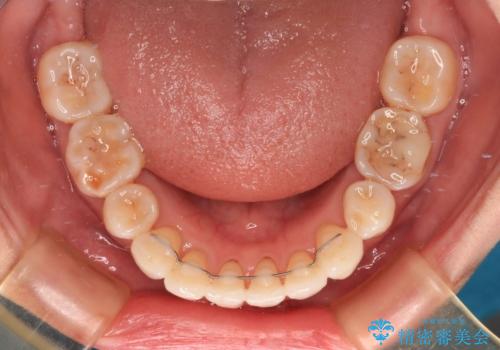

- 上の前歯の出っ歯を治したいとのことで来院された患者様です。

後戻りによる再矯正というもともあり、インビザラインを希望されていました。

上顎の歯は後方移動とIPR(歯と歯の間を削る)によって口元が引っ込むように、下顎は歯列全体の拡大とIPRによって上顎とバランスよく咬み合うように設計し、インビザラインにより治療を行うこととしました。